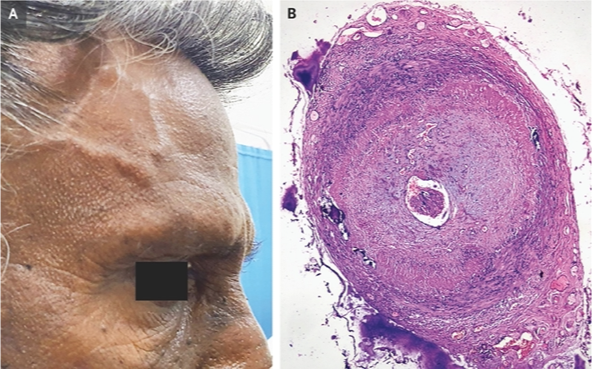

Giant Cell (Temporal) Arteritis - (Visibly enlarged temporal artery)